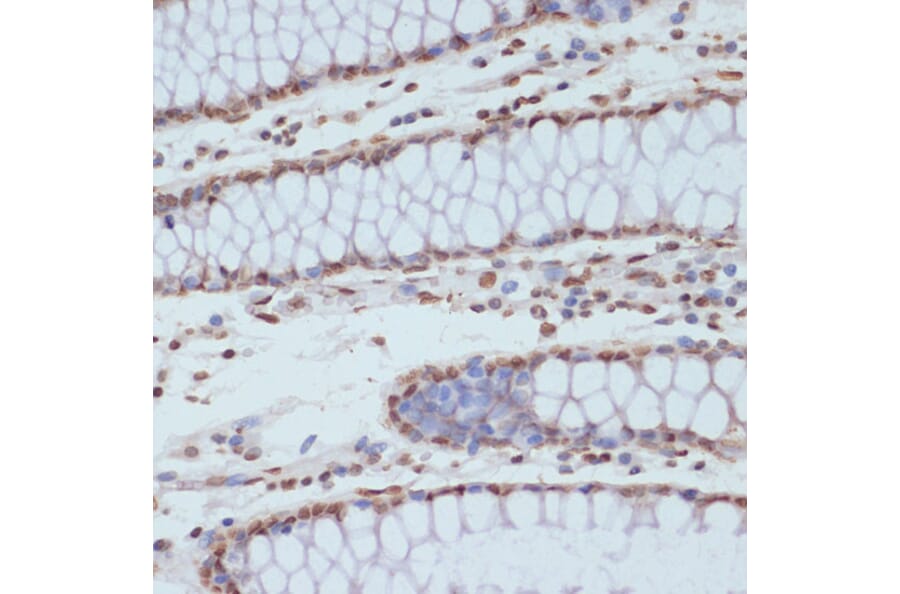

Immunohistochemistry analysis of paraffin-embedded human colon tissue using Anti-CDK1 (phospho Tyr15) Antibody (A16400) at a dilution of 1:100 (40x lens). Perform microwave antigen retrieval with 10 mM Tris/EDTA buffer pH 9.0 before commencing with IHC staining protocol.